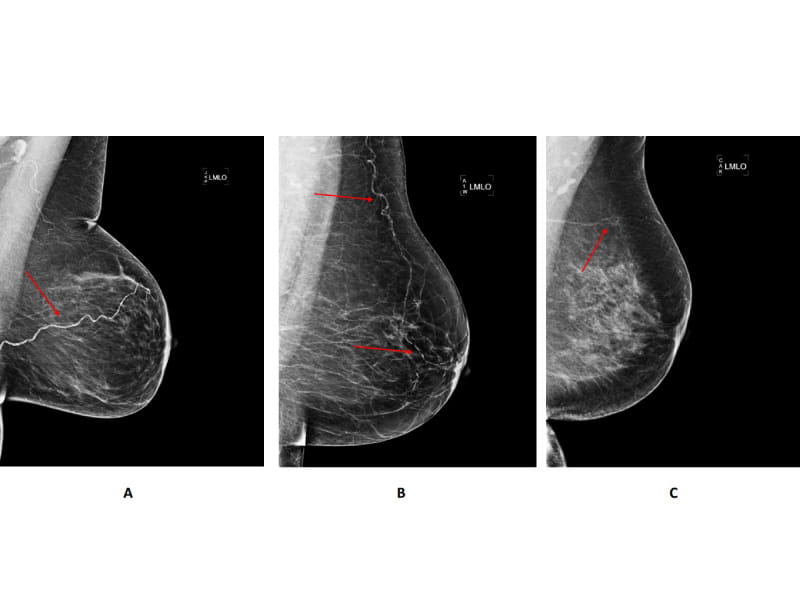

Routine mammograms are used to check women for breast cancer. But new research suggests they could do more than that: The images may help predict a woman's risk for major cardiovascular problems, such as heart attacks and strokes, when they show the presence of calcium buildup in the arteries of a woman's breast.

Her study builds upon a growing body of evidence suggesting screening mammograms may prove a useful tool for predicting cardiovascular risk because they reveal the presence of breast artery calcification, or BAC. Prior research has established BAC as a risk factor for cardiovascular disease.